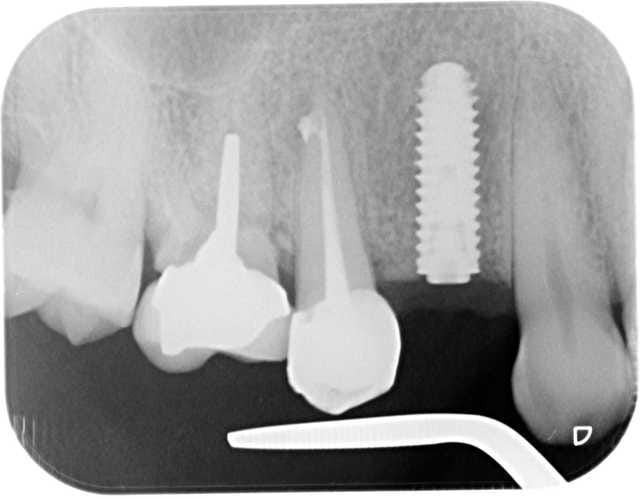

pose d'un axiom en 4*12 en juillet en sous crestal comme il le faut.

et aujourd'hui raido début de cratérisation : petite mais existante;

pour la forme et le fond pano avant retro à la pose et rétro aujourd'hui

prévu implant en 36 et l'endo de 15 avait été reprise avant pour être refaite simultanément je connais les critiques nonoliennes.

et la 16, on ferme les yeux......

pour info déja trois cas similaires au maxillaire pas à la mandibule.

et c'est un axiom en 4*12 pas un krestal